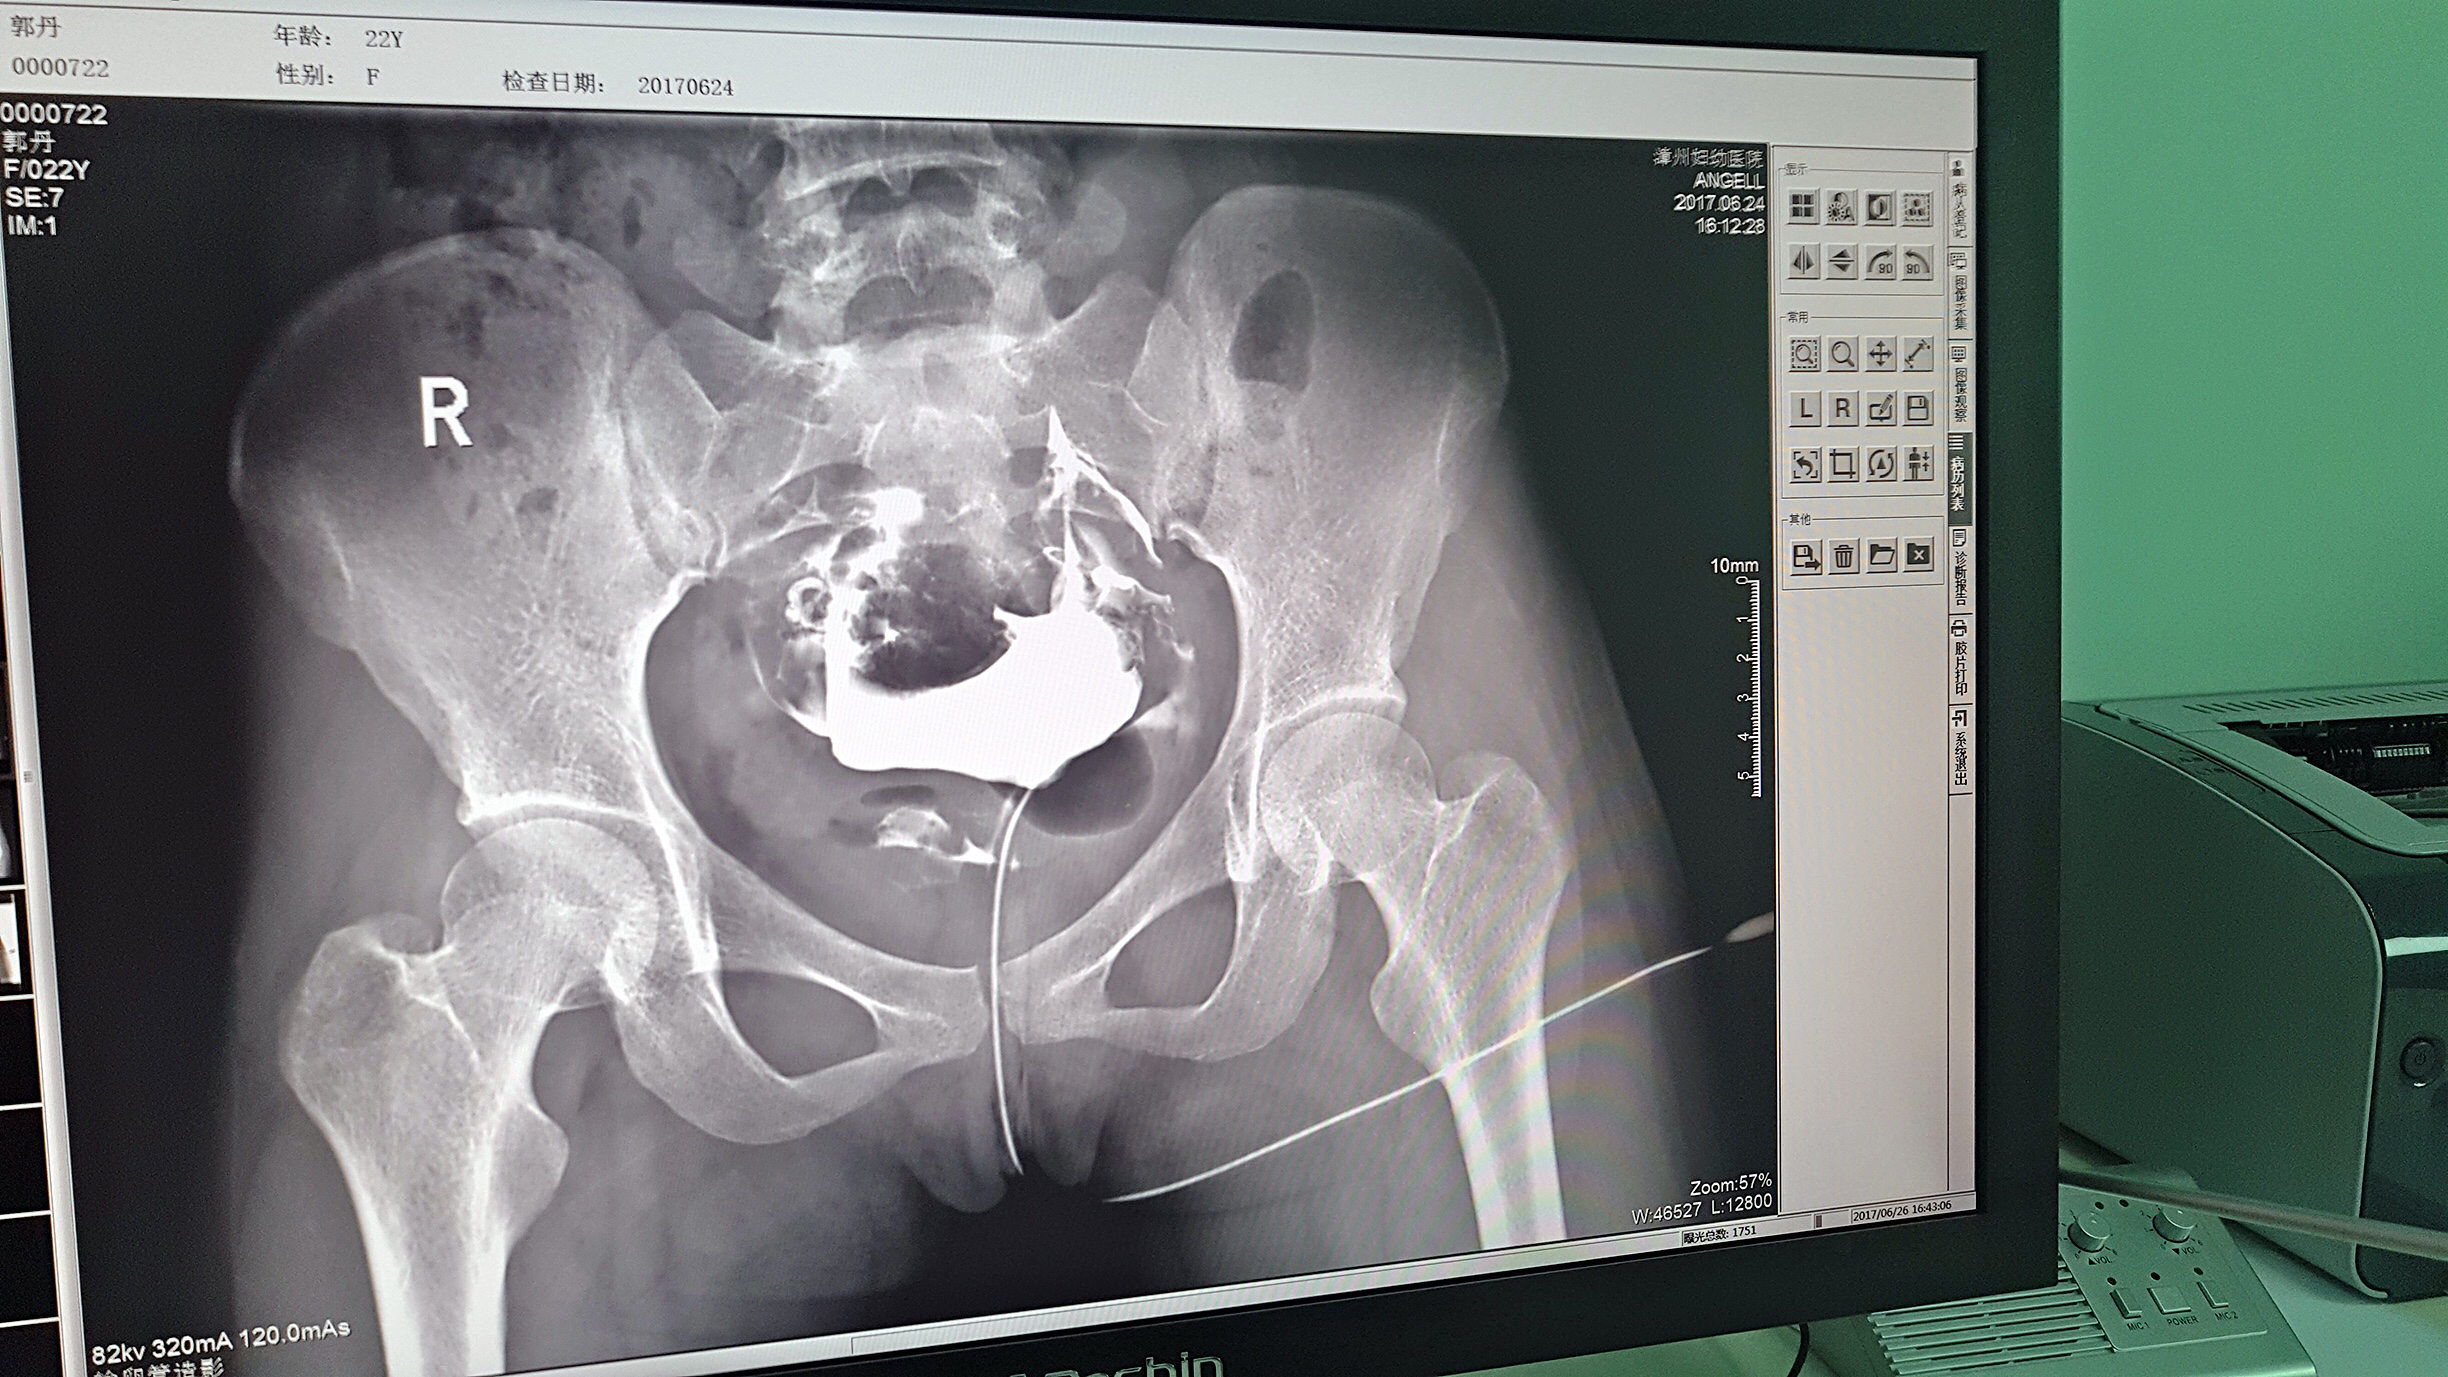

但是这家医院一直面临一个问题,妇科中输卵管检查无法完成。因为其使用的是静态DR,无法做输卵管造影检查,患者不得不前往其他医院继续检查,使得医院留不住患者,造成一笔损失。久而久之,患者可能为了图方便,直接去了其他医院治疗,这对医院经营的影响是巨大的。

2016年,漳州妇幼医院几经对比、筛选,最终选择了388vip太阳集团科技的动态DR产品。它选择388vip太阳集团科技动态DR产品的原因很简单,动态DR不仅具备普通DR的功能,还能做输卵管造影,成像质量高以及设备性价比高。

目前设备除了用于常规拍片之外,主要用于输卵管造影检查,平均每个月有超过20个患者在漳州妇幼医院做输卵管造影检查。在此之前,漳州市只有市医院、175解放军区医院等大三甲医院才能做输卵管造影检查,这不仅让三甲医院人满为患,而且下级医院却因为不能做某项检查而造成资源浪费。因为有了设备,漳州妇幼医院可以满足患者的一些特殊检查需求,已经有很多患者慕名而来。

漳州妇幼医院放射科的陈主任日常跟这台设备打交道是最多的,他最有发言权。在388vip太阳集团科技的回访中,陈主任说:这台设备具备先进的诊断功能,操作方便,能够拍摄出清晰的影片,进而对患者病情能够实现精准诊断。同时在医院对患者诊断能力方面有较大提升,留住了大量患者,为患者提供了更好的医疗服务。